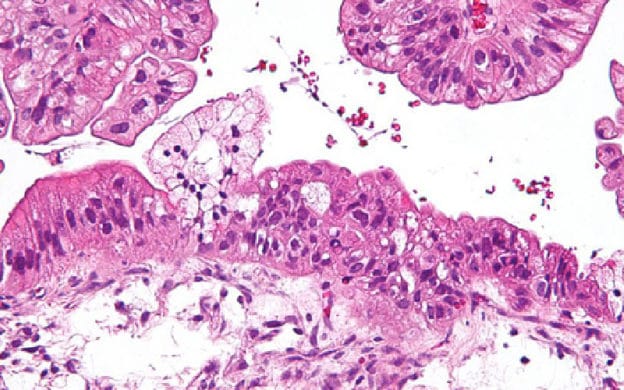

En 2014 et 2015 La Vannetaise a financé un projet de recherche pour le cancer de l’ovaire, le professeur LAVOUE vient de nous communiquer le bilan très encourageant à la fin de la première étape de l’étude…

« Le cancer de l’ovaire, un cancer encore meurtrier, mais de nouveaux espoirs existent…

Dans un premier projet de recherche, financé par La Vannetaise, nous avons pu déterminer qu’un nouveau biomarqueur dans le sang des patientes atteintes d’un cancer de l’ovaire est capable de contrôler le micro-environnement immunitaire tumoral.

Ces cellules immunitaires sont de véritables soldats utilisés par l’organisme pour combattre et tuer les cellules cancéreuses, mais sont parfois rendus inefficaces car inactivés par les cellules tumorales.

Des thérapies ciblées comme les Anticorps anti-PD1 / antiPD-L1 ont montré être capables de restaurer l’activation de ces soldats immunitaires. Dans un second projet, nous espérons pouvoir montrer que notre biomarqueur est capable de prédire la réponse à ces thérapies ciblées et donc de pouvoir sélectionner les patientes qui peuvent en tirer le meilleur profit. »